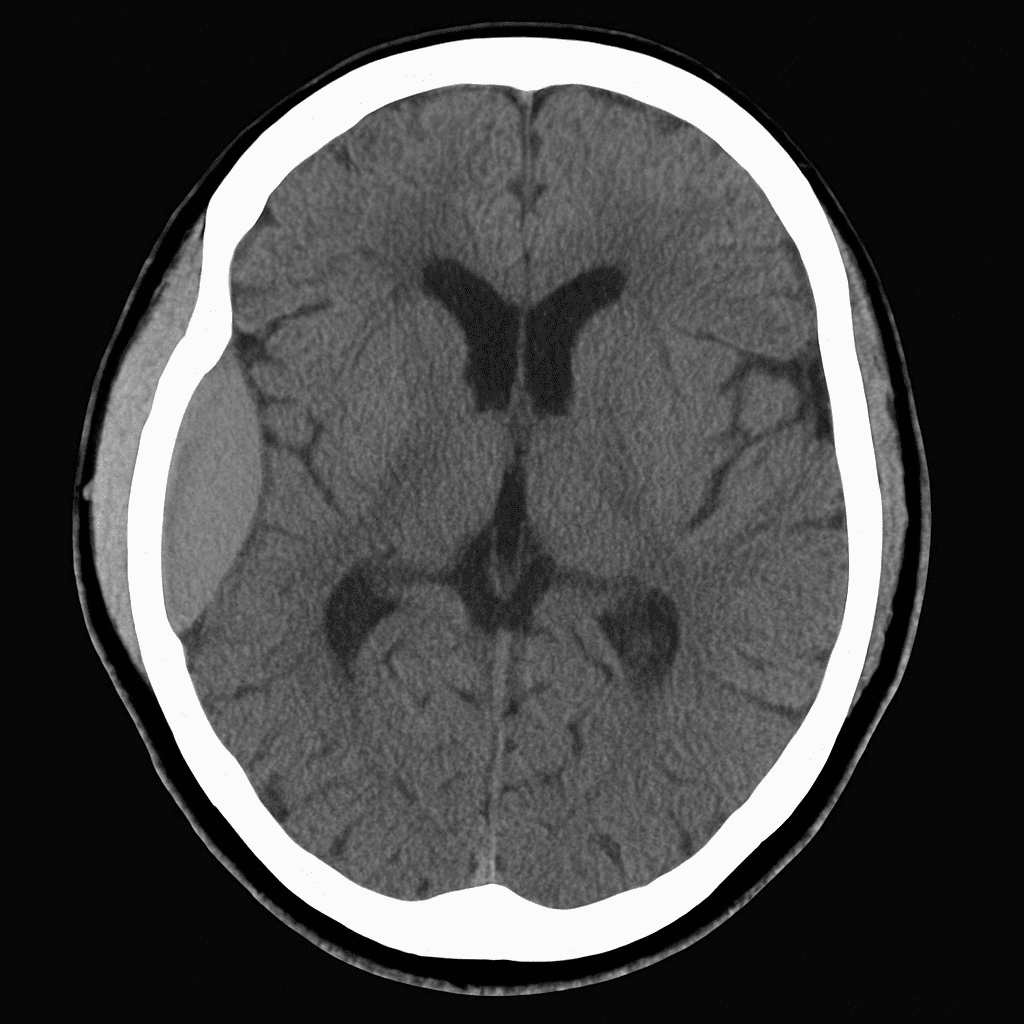

A 76-year-old man is brought to the emergency department after being found confused at home. He lives alone and his neighbour reports that he had a minor fall about two weeks ago but did not seek medical attention. On examination, he is slow to respond and has a mild right-sided weakness. His vital signs are stable. A non-contrast CT brain is performed and shown below.

Which of the following is the most likely diagnosis?

A) Acute intracerebral haemorrhage

B) Chronic subdural haematoma

C) Extradural haematoma

D) Acute ischaemic stroke

E) Brain abscess